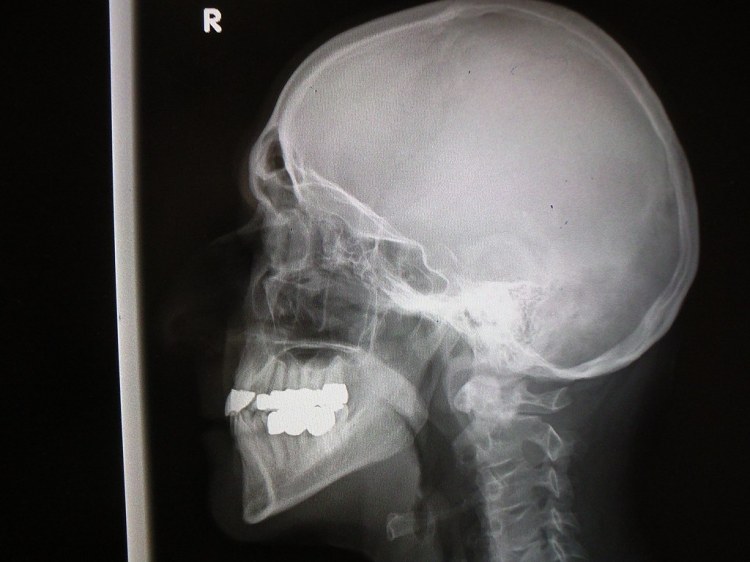

X-ray skull - Erich Ferdinand - FlickrEcharemos un vistazo a los diferentes tipos de procedimientos de imágenes y su dosis efectiva para un adulto de tamaño promedio. La dosis de cada radiografía se compara con la radiación de fondo natural a la que todos estamos expuestos a diario.